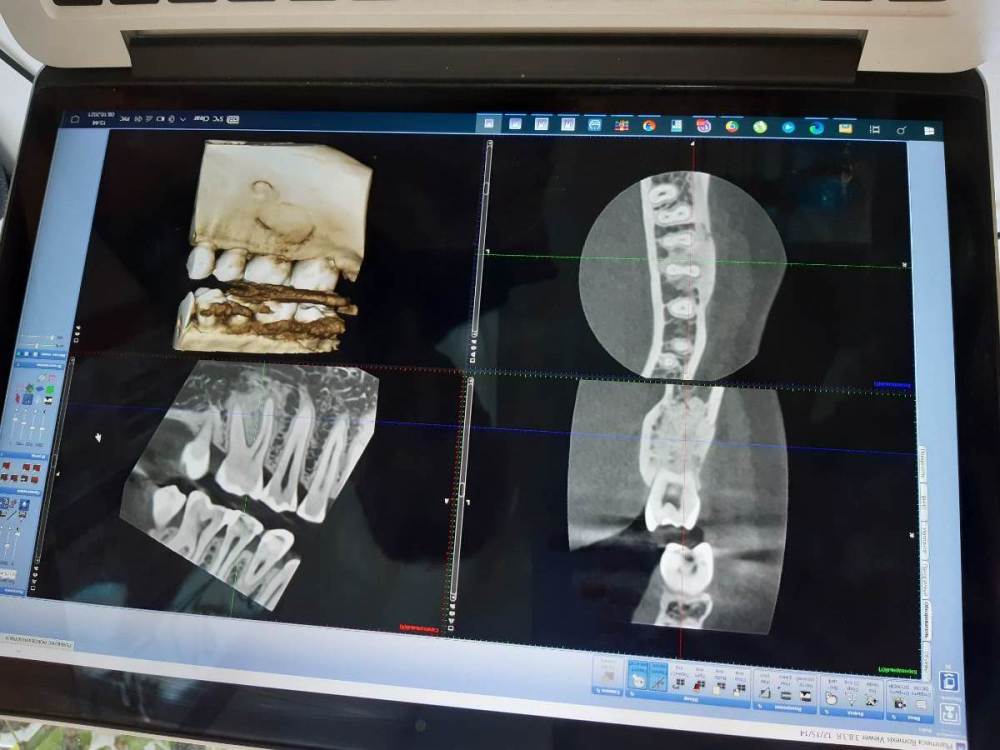

Lyubanya Опубликовано 8 октября, 2021 Поделиться Опубликовано 8 октября, 2021 (изменено) Коллеги, очень нужен ваш совет по поводу данного образования. Разница между снимками полгода. Симптоматики нет никакой. Кажется, есть тенденция к росту. Есть ли хоть шанс спасти зуб? Потеряла шестерку с другой стороны 10 лет назад, куча проблем теперь. Терять еще и этот уже как трагедия((( 31.03.21 7.10.21 Изменено 8 октября, 2021 пользователем Lyubanya Ссылка на комментарий

kriokov Опубликовано 13 октября, 2021 Поделиться Опубликовано 13 октября, 2021 20 часов назад, Lyubanya сказал: На холод реакция зуба есть) Рогацкина надо Вам активировать, он рентгенолог. На мой взгляд рентгенологически похоже и на цементно-костную дисплазию и на остеит. Ссылка на комментарий

Lyubanya Опубликовано 13 октября, 2021 Автор Поделиться Опубликовано 13 октября, 2021 8 часов назад, kriokov сказал: Рогацкина надо Вам активировать, он рентгенолог. На мой взгляд рентгенологически похоже и на цементно-костную дисплазию и на остеит. Рогацкина пинаю)) Были трудности с доступом файлов через гугл диск, потом поковыряла настройки и все наладилось. Пнула вчера, ответил что где-то в дороге. Пну завтра еще) Я тоже по снимкам тут, на форуме, посмотрела что на дисплазию похоже. Один из хирургов ставил остеому под ? Ссылка на комментарий

kriokov Опубликовано 13 октября, 2021 Поделиться Опубликовано 13 октября, 2021 3 часа назад, Lyubanya сказал: Рогацкина пинаю)) Были трудности с доступом файлов через гугл диск, потом поковыряла настройки и все наладилось. Пнула вчера, ответил что где-то в дороге. Пну завтра еще) Я тоже по снимкам тут, на форуме, посмотрела что на дисплазию похоже. Один из хирургов ставил остеому под ? не думаю, что остеома Ссылка на комментарий

Lyubanya Опубликовано 15 октября, 2021 Автор Поделиться Опубликовано 15 октября, 2021 13.10.2021 в 09:35, kriokov сказал: Рогацкина надо Вам активировать, он рентгенолог. На мой взгляд рентгенологически похоже и на цементно-костную дисплазию и на остеит. Наконец-то "допиналась" до финала? 2 Ссылка на комментарий